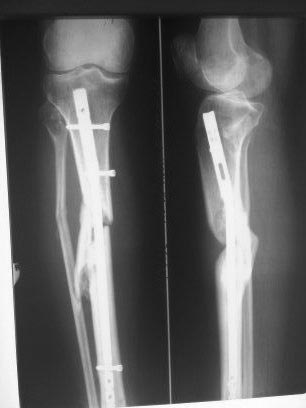

Пациентка 37 лет. Лечилась оперативно по поводу оскольчатого перелома обеих костей правой

голени, произведено БИОС, гвоздь 9. Через 2 мес. произведена динамизация, ходила с полной нагрузкой на

конечность. Место перелома не открывалось. Через 11 мес несращение. Больная жалоб никаких

не предъявляет. Ходит без дополнительных средств опоры, почти не хромает. Что делать? Заранее спасибо!